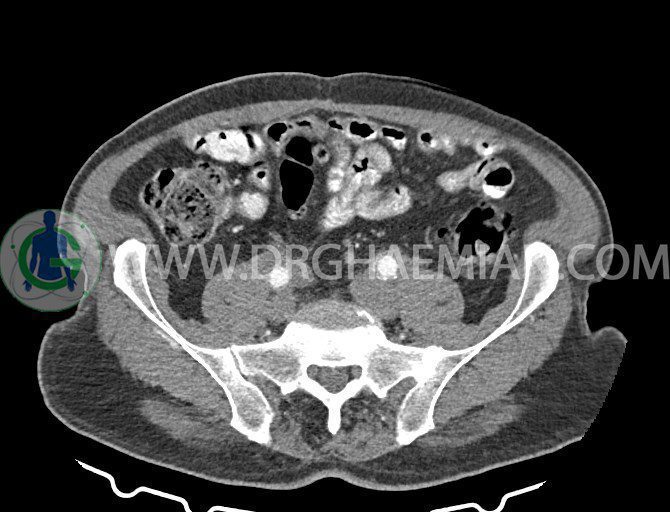

سی تی اسکن لگن یکی از روش های تصویربرداری با سی تی اسکن است. این روش با استفاده از تشعشعات تصاویر عرضی از ناحیه شکمی ایجاد میکند. در این کیس ديورتيكولوزيس، کیست های کورتیکال در هر دو کلیه، لنفادنوپاتی، کلسیفیکاسیون دیواره آئورت و شریان ایلیاک، تغییرات DJD ناحیه توراکولومبار و پروستات بزرگتر از عادی دیده می شود.

در سي تي اسکن اسپيرال شکم و لگن با و بدون کنتراست خوراکی و وريدی (مولتي ديدکتور 16 با مقاطع ظريف و بازسازي هاي ساژيتال و کرونال):

– ديورتيكولوزيس در کولون نزولي وسيگموئيد

لنفادنوپاتي به ابعاد mm 22 x 25 مجاور شريان ايلياک خارجي چپ و به ابعاد mm 17 x 28 مجاور شريان ايلياک خارجي راست